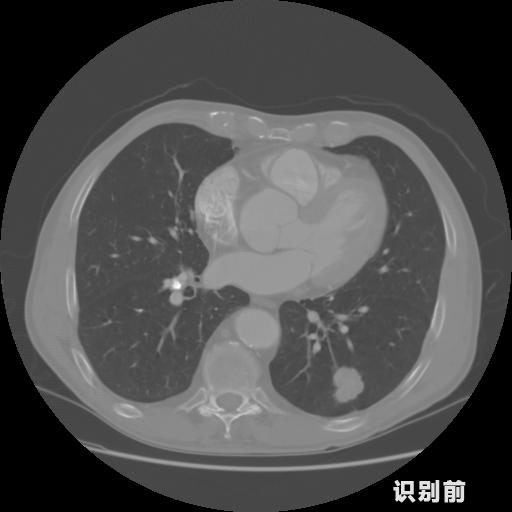

英特健康A(chǔ)I深度學(xué)習(xí)醫(yī)療圖像識(shí)別系統(tǒng)案例_胸部CT

03.jpg